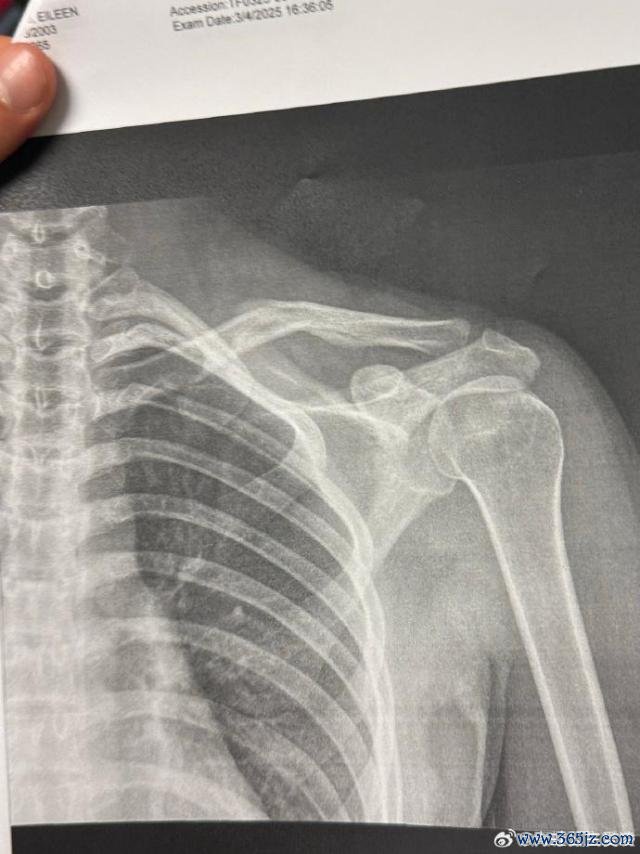

本年 3 月 9 日,谷爱凌在酬酢媒体晒出肩部骨折的 X 光相片,并配上一个心碎的色调,随后探求话题登上热搜。